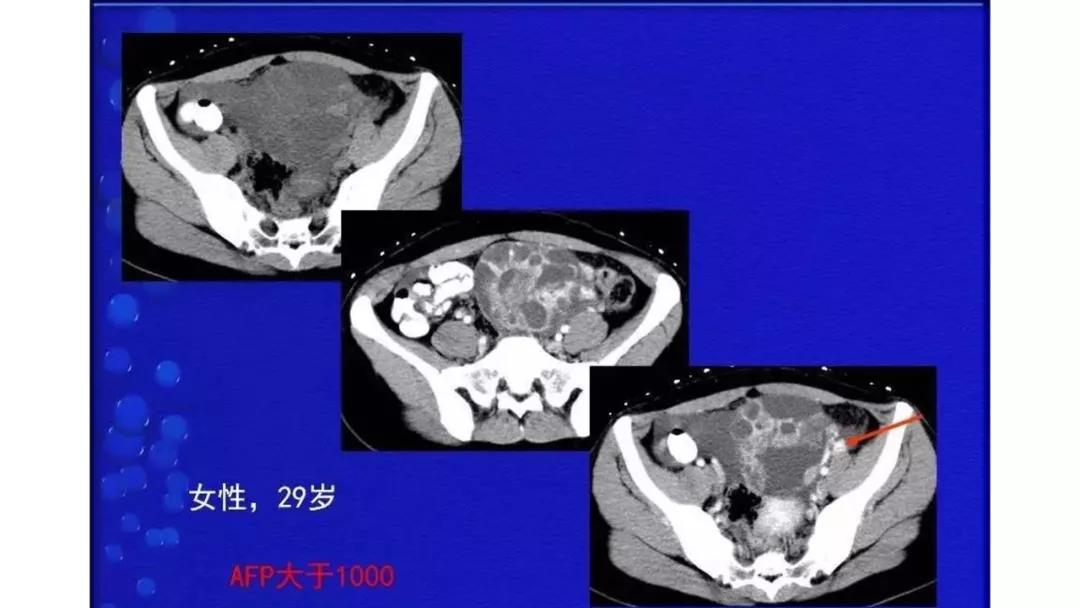

AFP升高:卵黄囊瘤、无性细胞瘤、混合瘤

恶性者常呈实性或混杂性肿块,多数边界清楚,可伴有不规则沙粒状钙化。无性细胞瘤常为实性肿块,轻度强化,内胚窦瘤实性成分明显强化,不成熟畸胎瘤呈混杂密度。结合年龄及临床生化检查,有助于诊断。